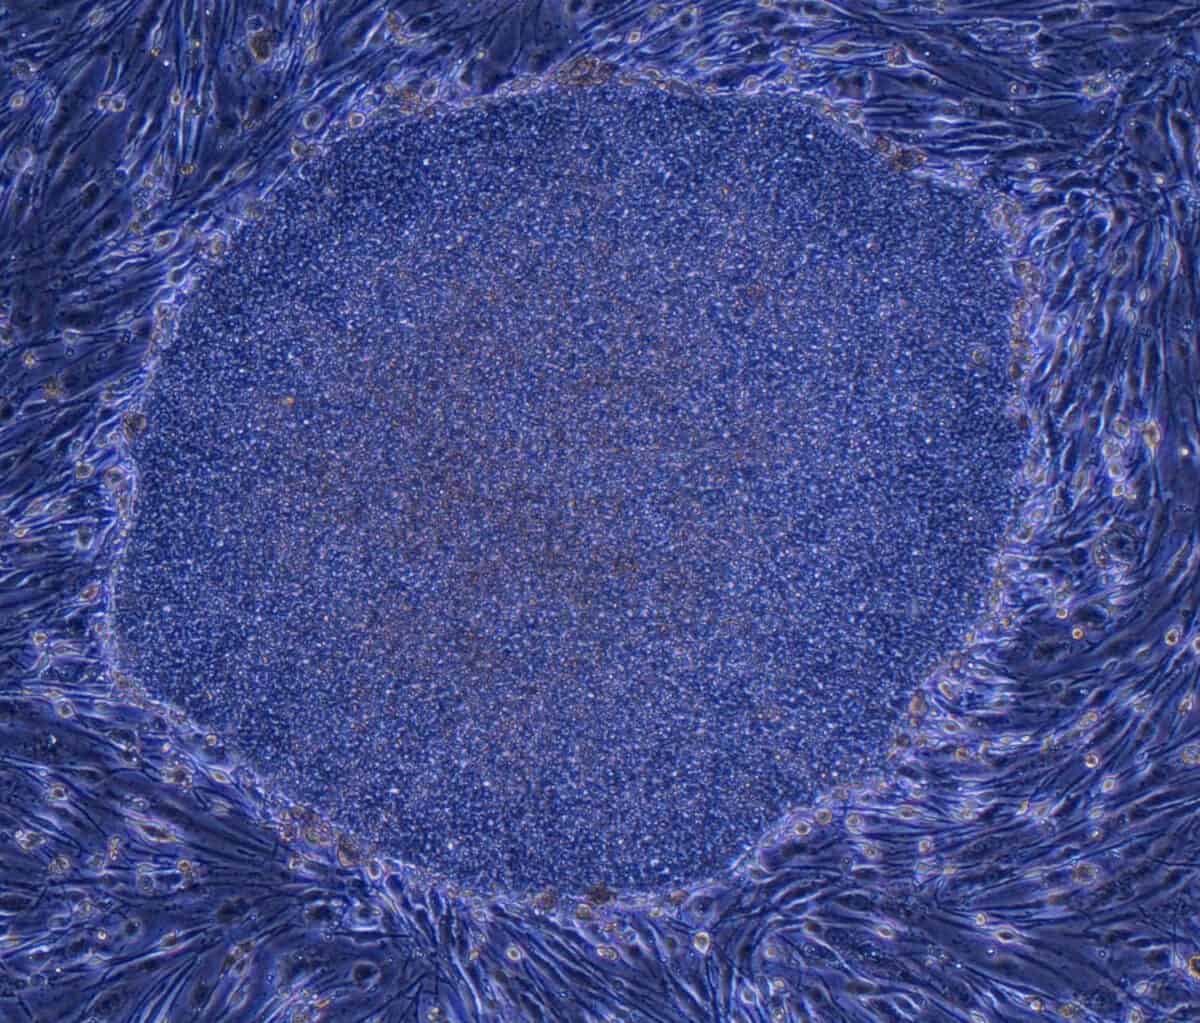

During the next two to three months, the cells began to organize themselves into layers and clusters of different cell types, paralleling what happens during the first eight to 10 weeks of human fetal brain development. Some cells differentiated themselves into various types of the nerve cells (neurons) found in several brain regions, while others remained “neural progenitors,” creating a reservoir of potential neurons to be used later. Producing such self-assembling organoids “doesn’t require any super-sophisticated bioengineering,” Knoblich told Nature in 2015. “We just let the cells do what they want to do, and they make a brain.”

Researchers had developed the technologies needed to create organoids years before—how to grow cells in culture, how to isolate stem cells from human tissue, and how to coax the stem cells, undifferentiated and immature, to become specific types of cells at later stages of development. But when such cells were grown in a laboratory dish, they adhered to the flat surface of the liquid medium they were grown on, spreading out in a thin layer. Confined to two dimensions, the cells couldn’t form the integrated structures of developing tissue.

Previous research had shown that if cells are grown in a medium called Matrigel—firm enough to support cells above a dish’s flat surface and pliable enough for cells to reshape as they grow and multiply—cells are able to develop in three dimensions as they would in the body, assuming the various shapes, layers, compartments and relationships within a particular organ. Clevers added his intestinal stem cells to this gel, and also introduced chemical growth signals that encouraged the stem cells to begin maturing. The intestinal organoids that grew from these elements developed several of the singular characteristics of that tissue type, including small knobby protrusions (crypts) that in full-size intestines serve as receptacles for stem cells.